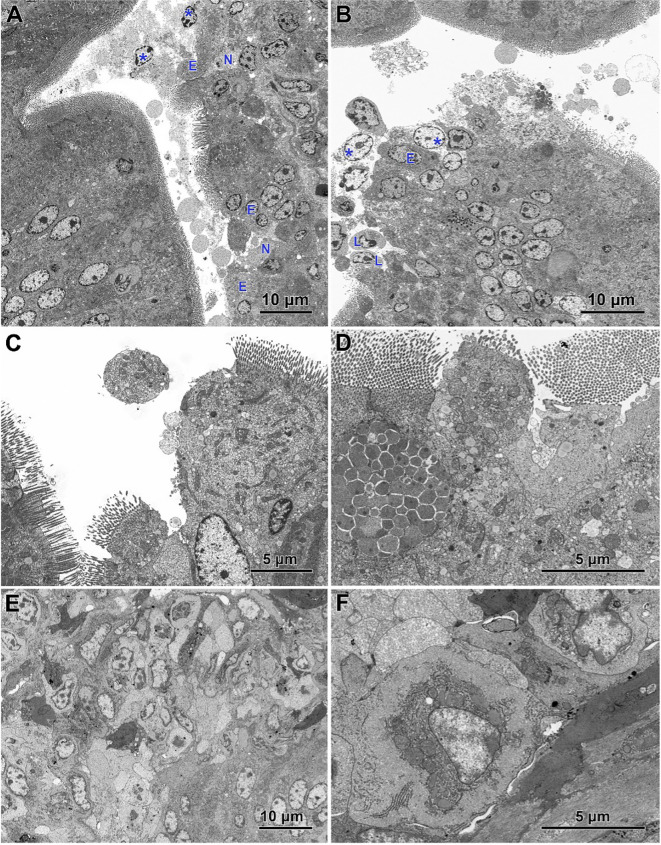

Electron microscopy revealed the presence of small necrotic regions within the epithelium covering both the apical and lateral surfaces of the intestinal villi in chickens infected with C. perfringens (f6). In addition to necrotic cells and cellular debris, these regions comprised abnormal enterocytes lacking cell polarity and microvilli. The cell debris was also present in the intestine lumen over the necrotic regions. The apical portions of villi, described at light microscopy level as devoid of the epithelium cover, contained necrotic cells, cellular debris, and numerous inflammatory cells, but also irregularly shaped enterocytes without microvilli (f6). Enterocytes in these areas were loosely attached and did not form the tight junctions. Ultrastructural analysis also revealed areas where enterocytes formed a continuous or nearly continuous layer but were highly irregular in shape and devoid of microvilli (f6). The stroma of some villi contained numerous inflammatory cells, frequently with foamy cytoplasm (f6) and an increased presence of smooth muscle cells (f6).

Infected chickens treated with CBD, CBD + nano-Se, or nano-Se displayed similar ultrastructural changes as those infected with C. perfringens but not supplemented with these compounds (f7). Necrotic foci covered with cellular debris (f7), areas of abnormal epithelium containing irregularly shaped enterocytes without microvilli (f7), intense infiltration of the epithelium by lymphocytes (f7), and the presence of inflammatory cells with foamy cytoplasm in the villi stroma (f7) were common across all infected groups receiving CBD, nano-Se, or CBD + nano-Se.